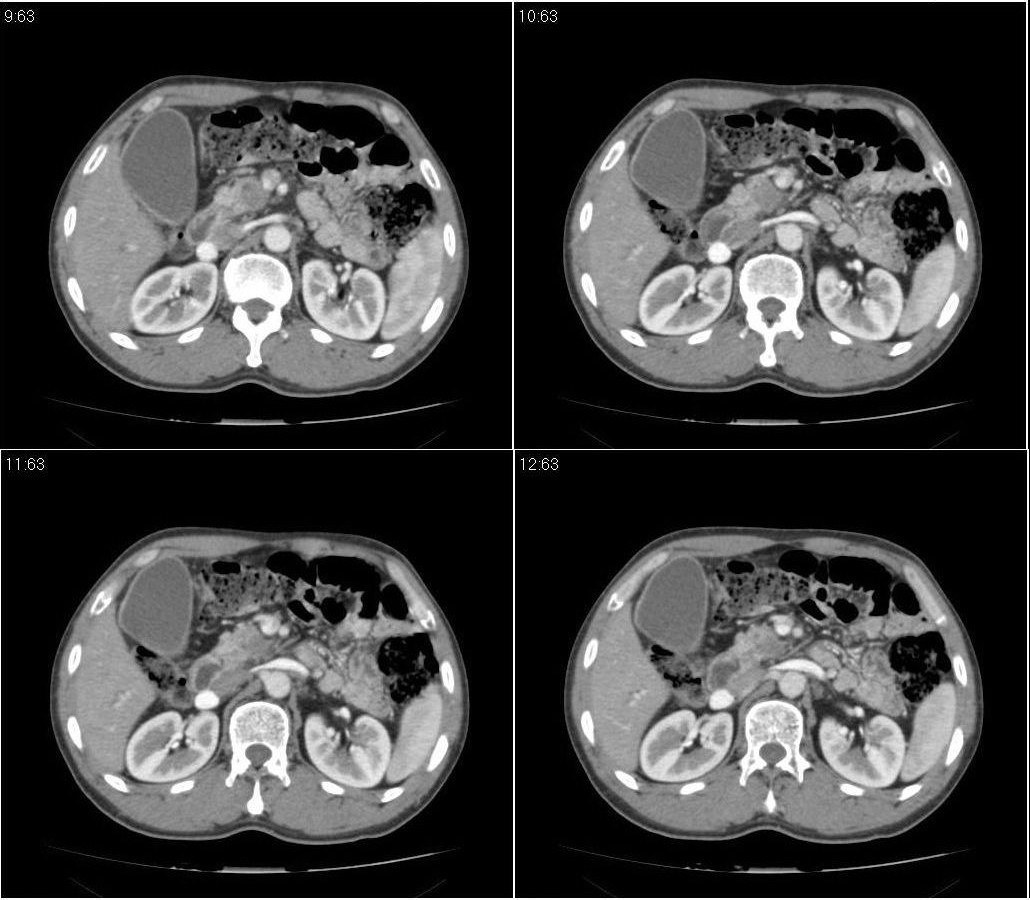

标题: CT21384:男性,50岁。发现无痛性黄疸十余天,B朝提示肝胆管 [打印本页]

标题: CT21384:男性,50岁。发现无痛性黄疸十余天,B朝提示肝胆管

1.考虑:壶腹占位病变(癌?)。

2.胆系低位梗阻:肝内外胆管扩张,胆囊增大,胰管扩张。

胰头癌伴低位胆道梗阻。

胆系低位梗阻(肝内外胆管扩张,胆囊增大,胰管扩张);考虑胰头癌或壶腹癌所致。

胰头强化欠均匀,胆胰管扩张。考虑胰头癌可能性大。

胆系低位梗阻(肝内外胆管扩张,胆囊增大,胰管扩张,钩突似有占位);考虑胰头癌